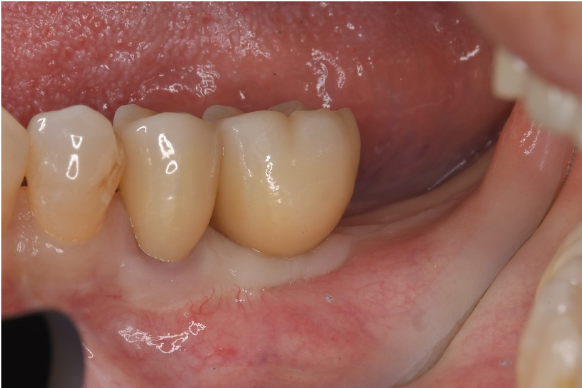

症例3

| 通院期間 | 9か月 |

| 来院回数 | 12回 |

| 治療費 | 総額:835,000円(税抜) 【内訳】 インプラント埋入手術250,000円、GBR(骨再生手術)150,000円、2次手術+FGG(遊離歯肉移植術)55,000+60,000円、仮歯30,000円、インプラント上部構造(セラミッククラウン)170,000円、隣在歯セラミッククラウンのやりかえ120,000円 |

| リスクと副作用 | 定期的なメンテナンスが必要、術後若干の腫れと痛み |

| ここがこだわりのポイント!☝ | インプラント周囲に角化歯肉と言われる健常な歯肉がなかったので、口蓋からの歯肉移植を行っています💡この角化歯肉がないと、インプラントをしてもうまく歯磨きができないことがあります。 |